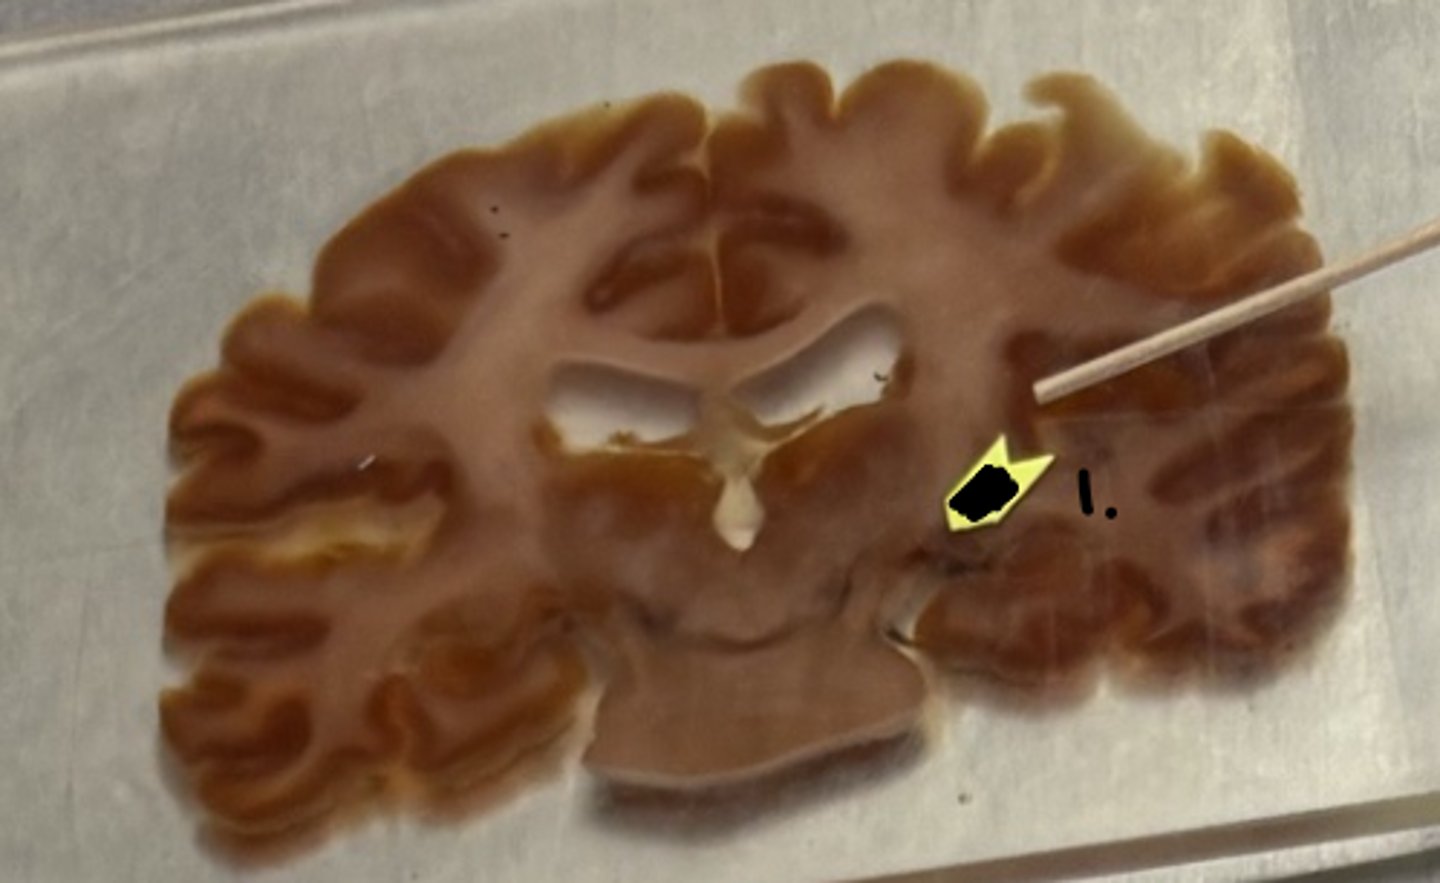

lateral geniculate nucleus

what structure is labeled as #1 ?